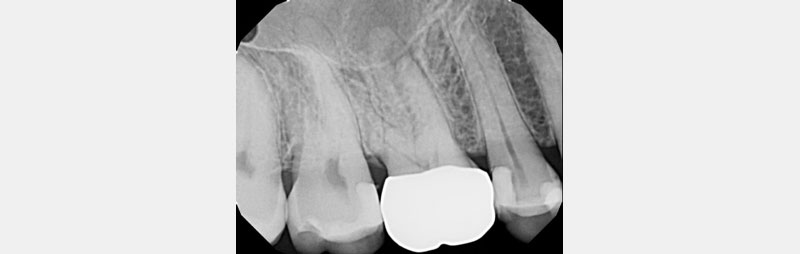

Sometimes the crown was just cemented and placed after being prepped and temped uneventfully, and the patient never reported any symptoms or discomfort (see Figs. 4–6). Often during crown treatment planning, (newer) PAs are not taken, and the crown gets prepped and temped based on the FMX from years earlier.

In Figs. 7–9, each patient was asymptomatic, but clearly all had medium- to large-sized restorations.